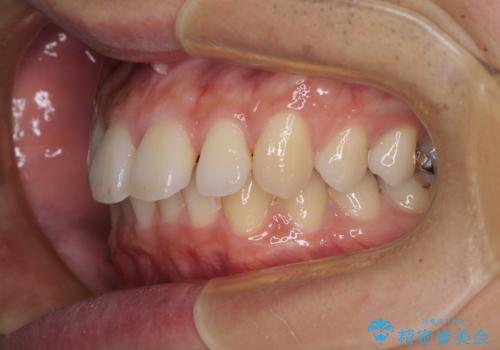

深い咬み合わせと前歯の隙間 ハーフリンガルによる矯正治療

- 咬み合わせにより上顎正中に隙間ができているとのことで来院された患者様です。

インビザラインは自己管理が煩わしく、表側のワイヤー装置は目立つので避けたいとのことで、上顎だけが裏側装置のハーフリンガルにて矯正治療を行うこととしました。